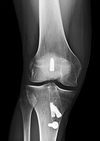

A

avulsion fracture of the fibula (arcuate fracture ) or femoral condyle